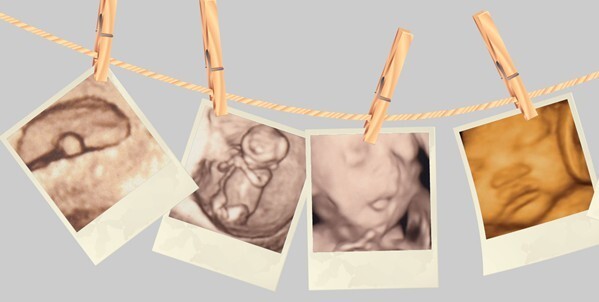

四维彩超检查是为了让您更直观的了解您宝宝在腹内的情况,对胎儿早期的畸形诊断有很好的效果。这项检查在孕期也是备受孕妈妈关注的,做彩超检查的准妈妈检查前不知道要做什么准备,下面为你介绍“在做四维彩超前要做哪些准备”。

福州台江医院的GE四维彩超,是彩色超声设备,被誉为“神奇彩超”,是筛查胎儿畸形的尖端设备,广泛应用于妇产科领域。四维彩超能够多方位、多角度、更清晰地观察宫内胎儿的生长发育情况,为早期诊断胎儿先天性体表畸形和先天性心脏疾病提供依据。

相比传统B超和早期四维彩超设备,四维彩超速度更快、信息量更大、成像更快、分辨率更高,不仅能检查胎儿的生理指标,还能对胎儿的体表进行检查,如唇裂,脊柱裂,大脑、肾、心脏、骨骼发育不良等进行详细检查。